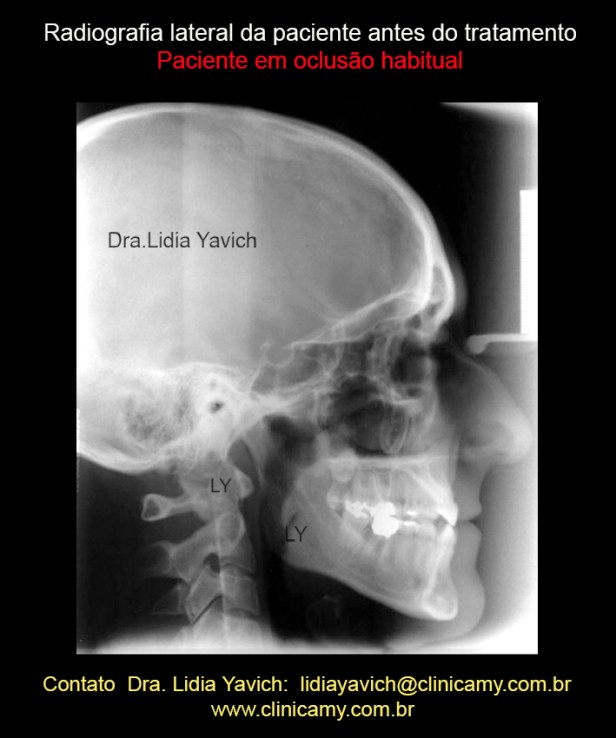

Radiografia lateral da paciente em oclusão habitual antes do tratamento.

Radiografia lateral da paciente em oclusão habitual antes do tratamento.

Radiografia lateral e da coluna cervical da paciente em oclusão habitual antes do tratamento. Nota-se a perda da lordose cervical, retificação da coluna cervical.

Radiografia lateral e da coluna cervical da paciente em oclusão habitual antes do tratamento. Nota-se a perda da lordose cervical, retificação da coluna cervical.